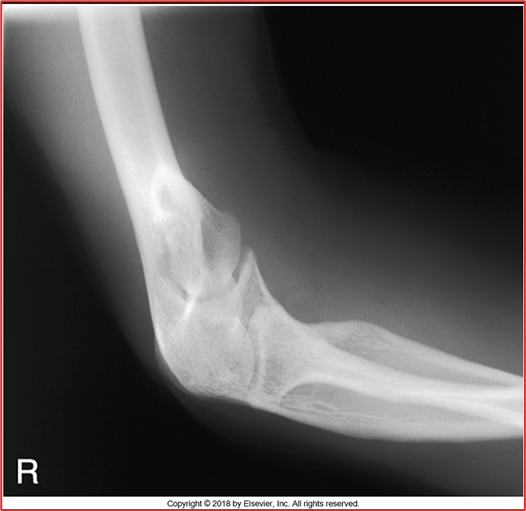

these 2 elbow images are in what position (2 for 1!!)

in this AP Partial Flexion is the humerus or forearm parallel

these 2 images of the elbow are in what position (2 for 1!) CR perpendicular to humerus and then CR perpendicular to forearm

this acute flexion of the elbow image is showing the __ __

what 2 position (2 images each) compromises for an AP elbow radiograph